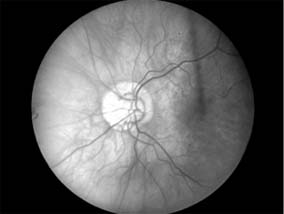

Figure 14-8

Figure 14-8: Mild disk swelling in demyelinative papillitis, with disk leakage on fluorescein angiography.